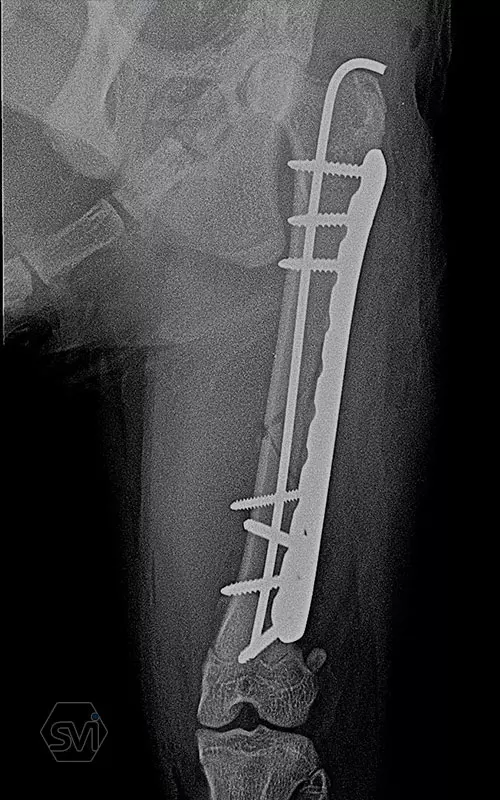

The plates are made in two types: the cutable ones, presented earlier, and the straight plates discussed here. The plates are made of 2 mm thin material and the hole is designed to accept the new 2.0 mm torx head threaded screws and the already used 2.4 mm torx head screws. As our case shows, the two screw sizes can be freely combined within one operation, according to the surgeon's needs. The screws require a T8 torx screwdriver. Of course, the plate can accept traditional AO screws as well.

In our case, a middle third fragment fracture of a 10-month-old kitten was treated with a 2.0 polyaxial plate and a combination of 2.0 and 2.4 screws.

Esetünkben egy 10 hónapos cica középső harmadiszilánkos törését kezeltük 2,0 poliaxiális lemezzel és 2,0 és 2,4 csavarok kombinációjával.